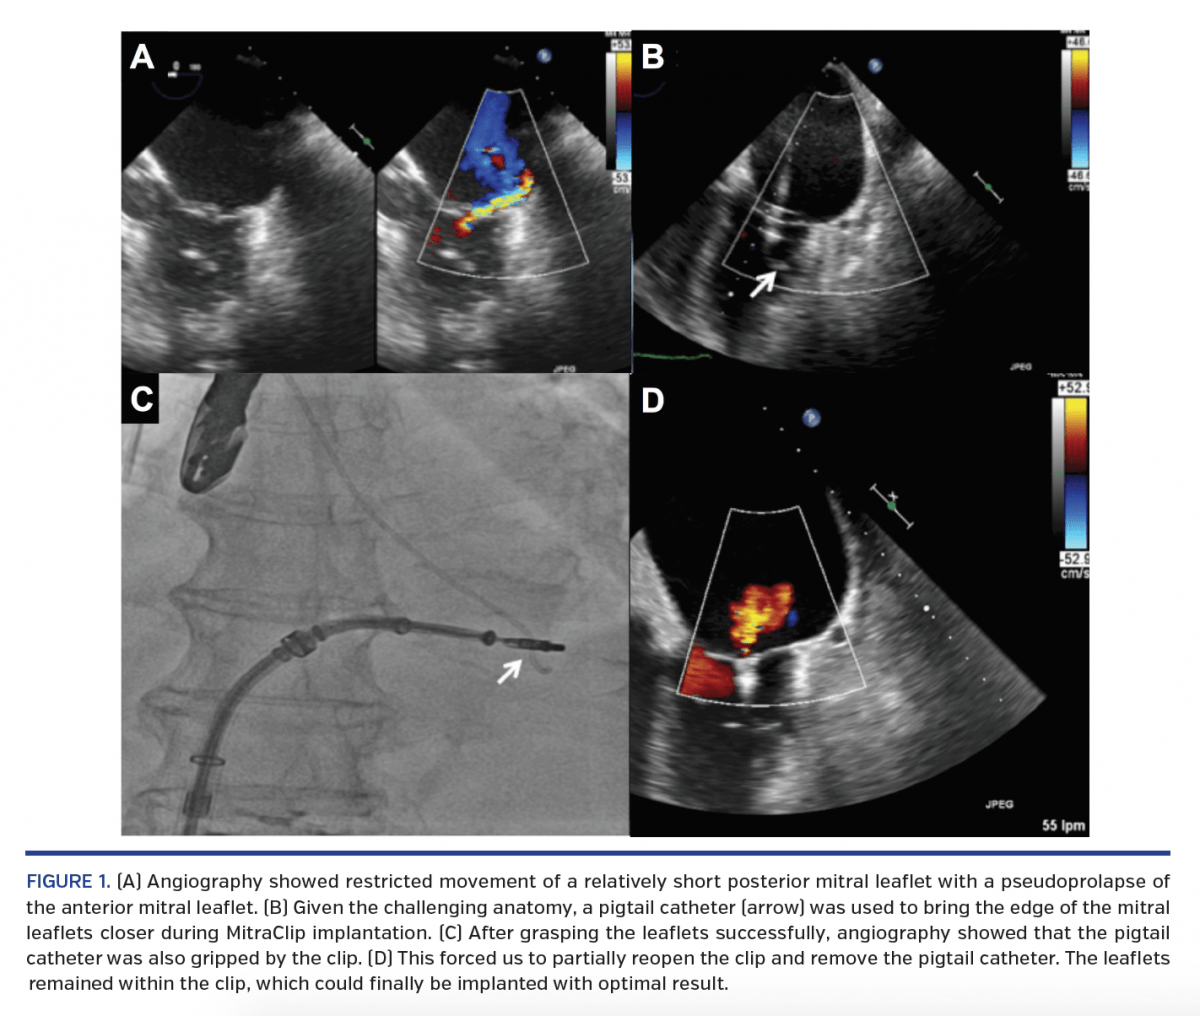

Catheter Entrapment During Posterior Mitral Leaflet Pushing Maneuver Catheter Entrapment Arterial spasm is a complication of cardiac catheterization unique to the. During tr procedures, aggressive catheter manipulation in the setting of complex and tortuous arterial anatomy can lead to. Intracoronary ultrasound (ivus) facilitates optimal stent deployment in the treatment of coronary artery disease, which may favorably improve. Technique for catheter kink management via swallowing with longsheath. Entrapment of catheter remnants. Catheter Entrapment.